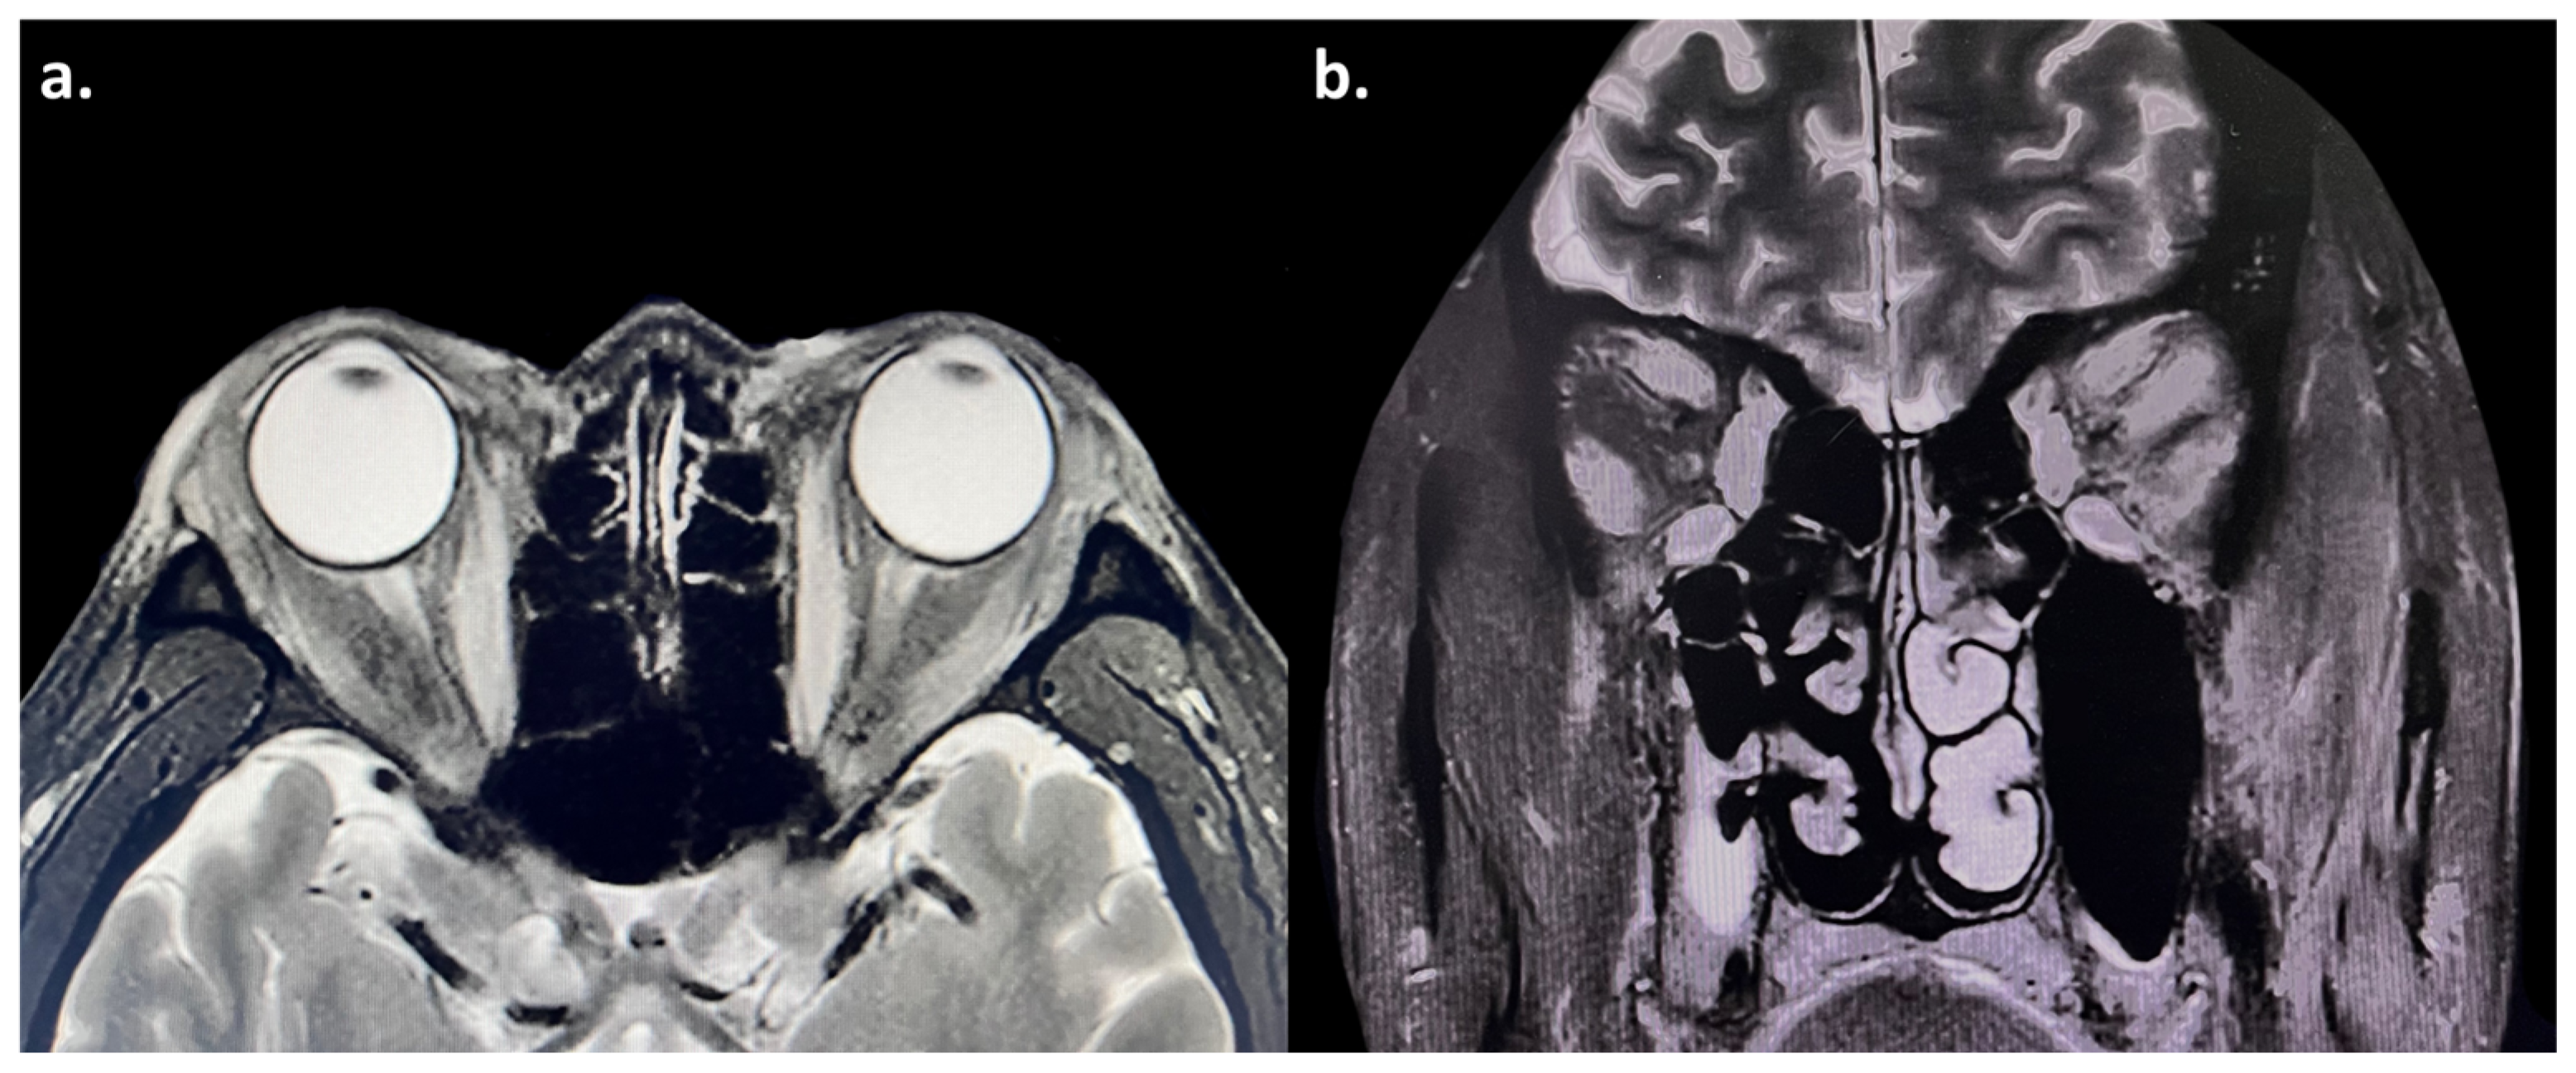

2. Case Report